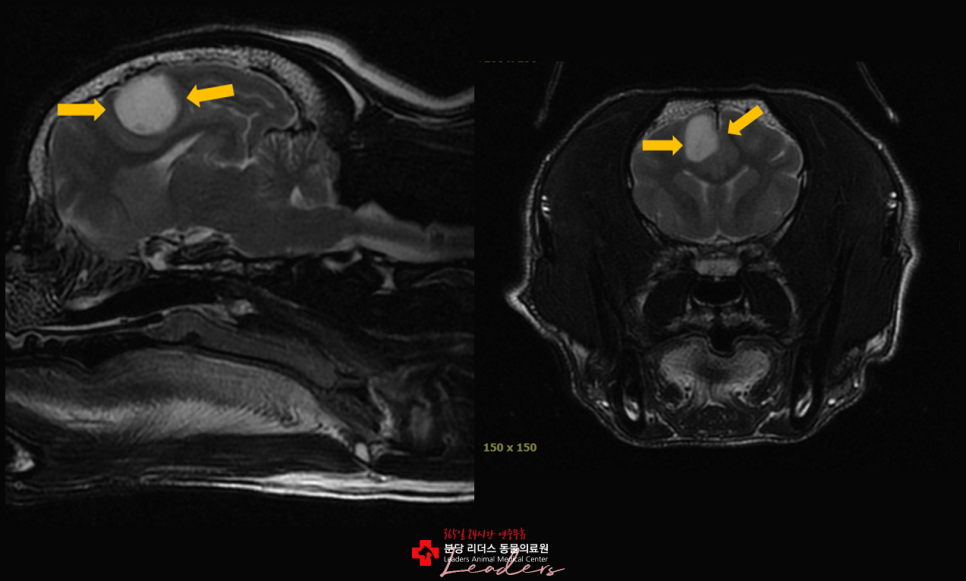

MRI 기반 정확 진단

반려동물의 뇌종양을 정확하게 평가하기 위해 사용되는 핵심 영상 진단 장비입니다.

MRI는 뇌 조직의 미세한 구조와 병변을 고해상도로 촬영할 수 있어, 종양의 위치·크기·경계는 물론 주변 신경 조직과의 관계까지 정밀하게 확인할 수 있습니다. CT나 X-ray로는 구분이 어려운 연부조직 변화까지 확인할 수 있어, 종양의 종류를 감별하고 수술 가능 여부접근 방향을 판단하는 데 중요한 기준이 됩니다.

뇌실종양

뇌실질종양